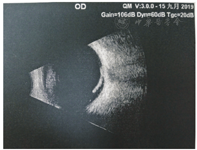

玻璃体腔可见积血,与视网膜相连,未见视网膜脱离

Vitreous hemorrhage can be seen in the right eye, which is connected to the retina. There is no retinal detachment.